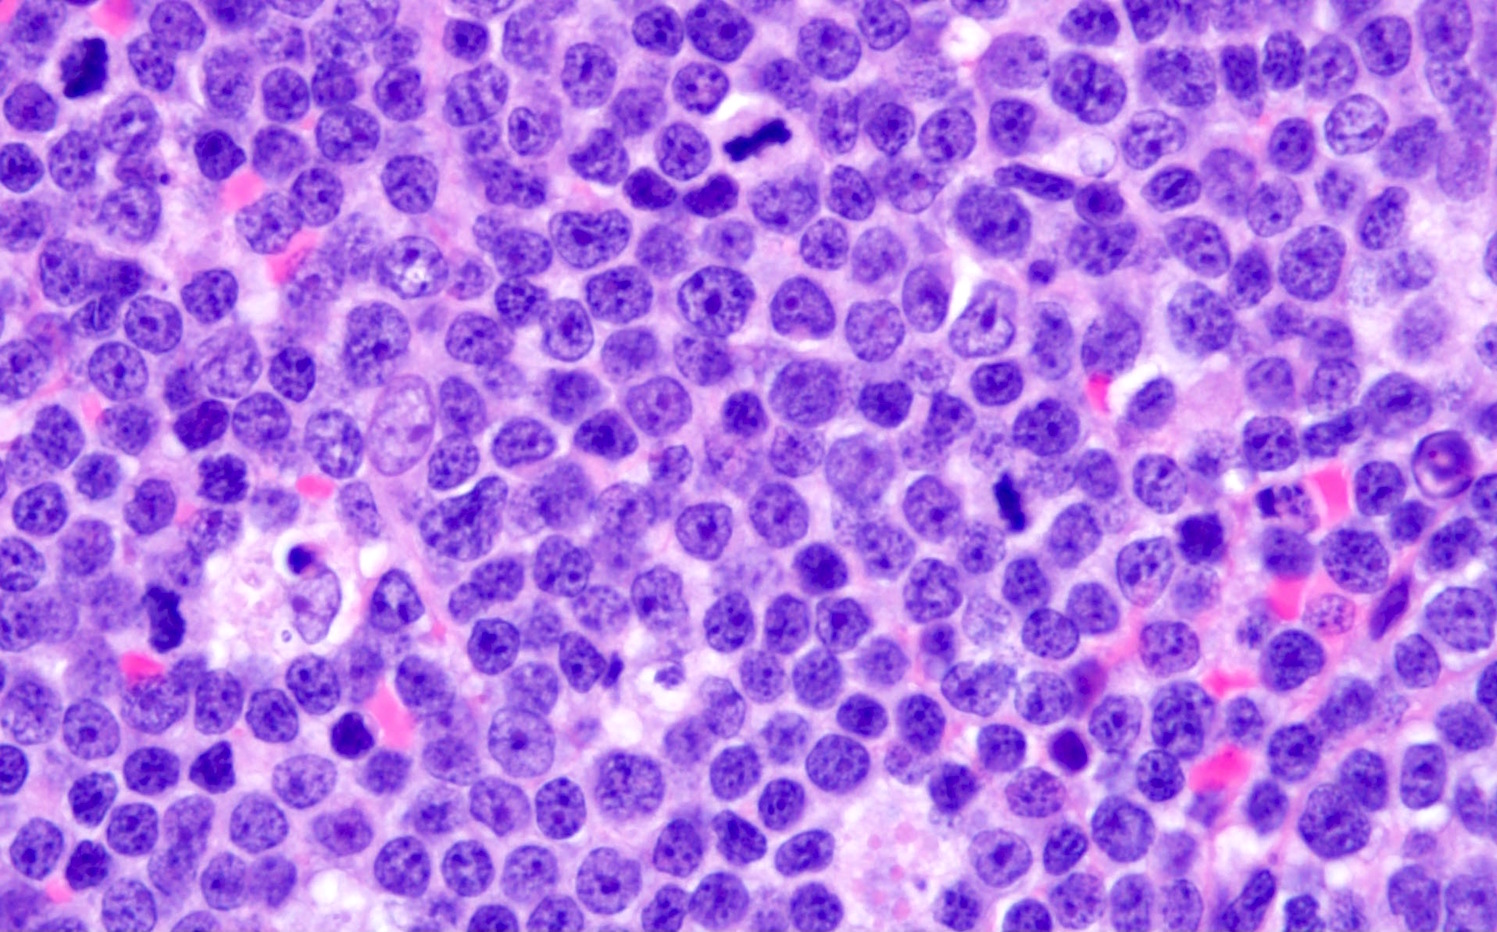

- Pleomorphic variant

- Variable size / heterogenous cell population including large cells

- Prominent nucleoli +/-

- High mitotic rate often seen

- At least 10 mitoses per 10 high power fields and often higher rates

- Resembles, in part, diffuse large B cell lymphoma

- Peripheral blood lymphocytes are intermediate sized with prominent nucleoli

- Resemble prolymphocytes to variable degree

- Multinucleation or cerebriform nuclei often seen

Microscopic (histologic) images